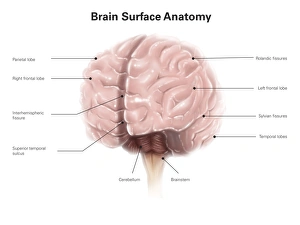

The central nervous system, the intricate network that governs our every thought and movement, is a marvel of complexity. From the delicate cerebellum tissue to the detailed light micrograph capturing its essence, we are reminded of its importance in maintaining balance and coordination. Anatomy comes alive as we explore the human brain from an inferior view. The intricacy of brain fibers is revealed through DTI MRI scans like C017/7099 and C017/7035, showcasing their vital role in transmitting information throughout this extraordinary organ. Artistic renderings bring us closer to understanding the medulla oblongata's significance within the brain. Its portrayal in various artworks allows us to appreciate how it controls essential functions such as breathing and heart rate. As we delve deeper into studying the central nervous system, models of the human brain provide invaluable insights into its structure and organization. Lateral views reveal countless regions responsible for cognition, emotion regulation, sensory perception, and motor control. Microscope slides offer glimpses into nerve cells' intricate architecture—a testament to their ability to transmit electrical signals at lightning speed. Meanwhile, glial stem cell cultures captured under a light microscope remind us of their crucial role in supporting neuronal function. Finally, artistic representations unveil the limbic system's enigmatic nature—an interconnected web responsible for emotions and memory formation. These captivating artworks allow us to visualize this complex network within our brains. Exploring these hints provides a glimpse into the awe-inspiring world of our central nervous system—the very foundation upon which our thoughts, actions, memories reside—reminding us just how remarkable our brains truly are.